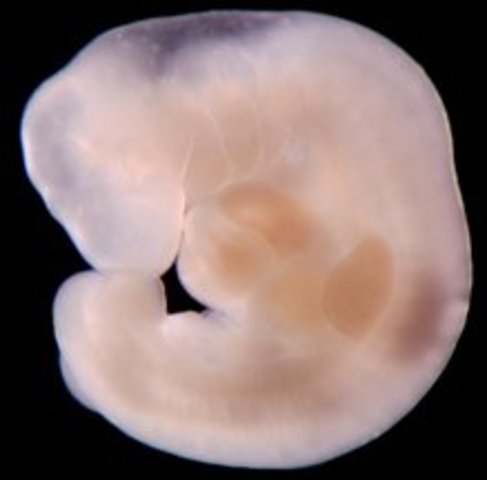

• Week Three: Cells Join, Divide - New life begins

Week Three: Cells Join, Divide - New life begins

The sperm travels through the Uterus and into the Fallopian Tube where it will penetrate and fertilize an egg. Sperm can live up to 5 days in this environment.

• Week Four: Implantation

Week Four: Implantation

When the egg is fertilized, it starts dividing and travels to the Uterus. It is here where the sex of the baby is determined.

• Week Five: The Embryonic Stage Begins

Week Five: The Embryonic Stage Begins

The Placenta is starting to develop. The embryo recieves oxygen and nutrients through the placenta.